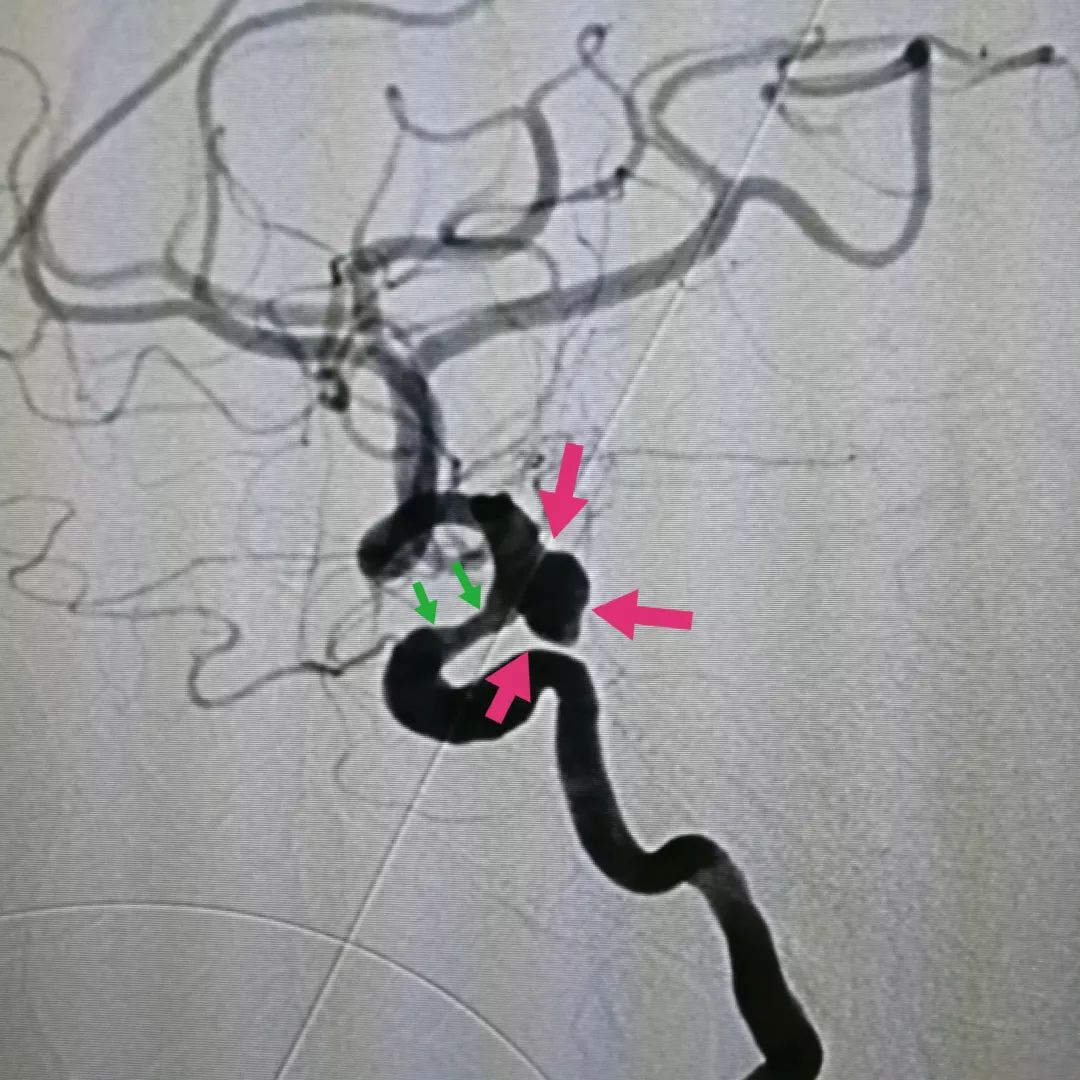

图二:2D血管造影可以见到动脉瘤位于颈内动脉末端,瘤体上有破口